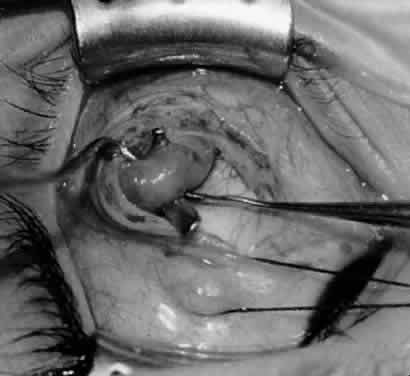

Fig. 21. A hemostat is placed adjacent to the insertion of the right inferior oblique muscle.

Fig. 22. An Aebli scissor is used to section the inferior oblique muscle from the globe.

Fig. 23. The inferior oblique muscle is drawn into the operative field with a hemostat. This step may be used for the recession procedure if the surgeon is concerned about the placement of the 6-0 Vicryl suture while the muscle is attached to the globe in the proximity of the macula. The recession sequence would follow after the placement of the suture while the muscle is grasped in the hemostat.